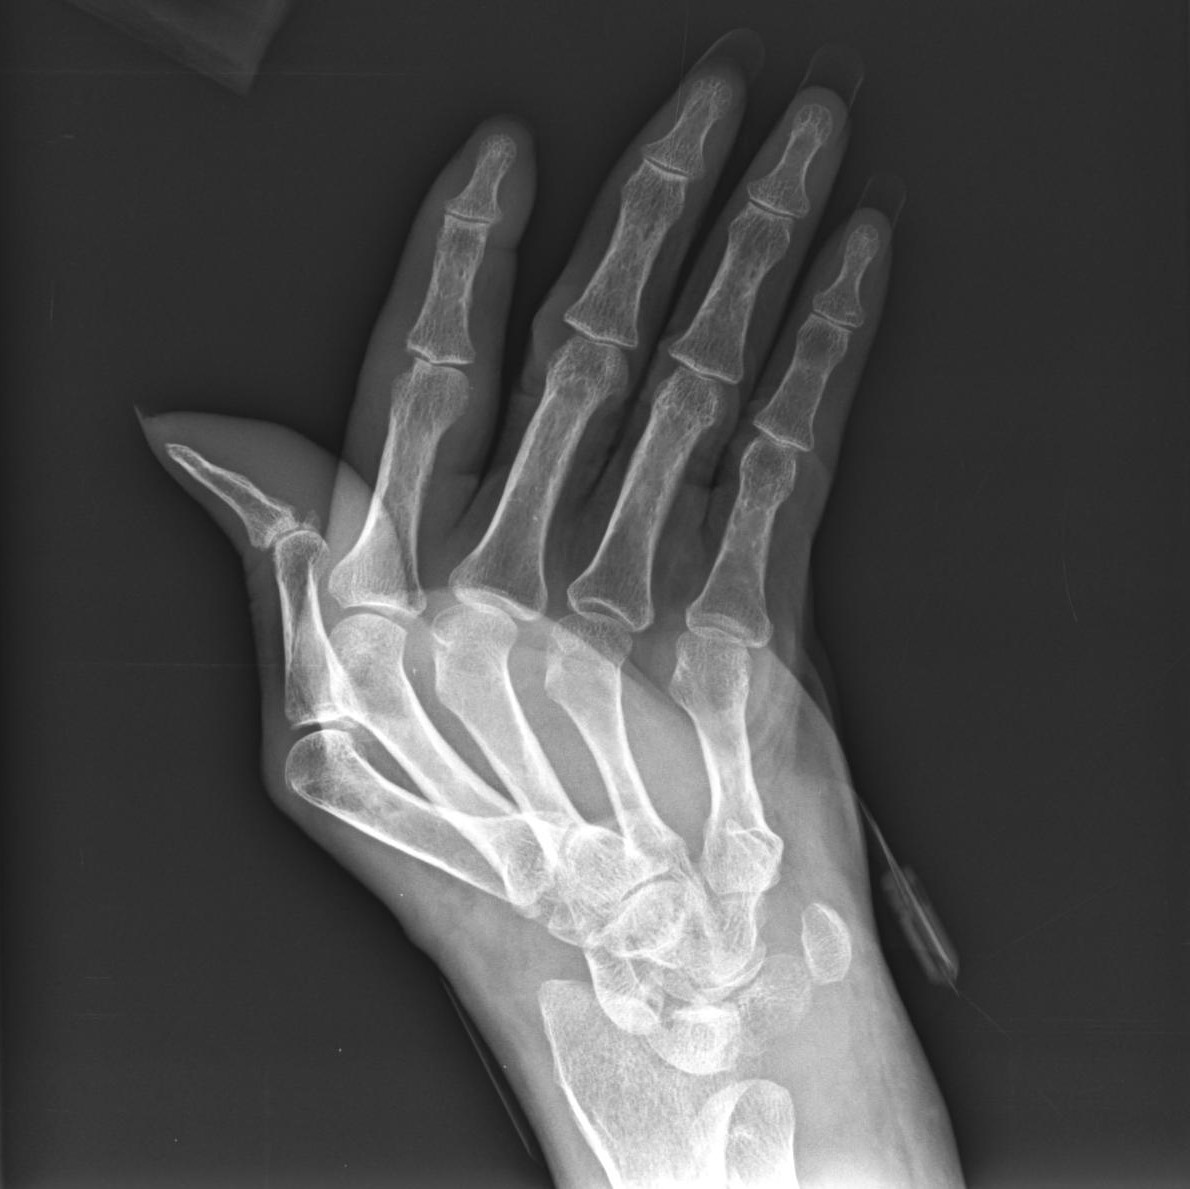

• Jaccoud’s Arthritis

• Jaccoud arthropathy is a deforming non-erosive arthropathy characterised by ulnar deviation of the second to fifth fingers with metacarpophalangeal joint subluxation.

• Jaccoud arthropathy is characterised by marked ulnar subluxation and deviation at the metacarpophalangeal joints that is correctable or reducible with physical manipulation

• Defomities can be corrected by the patients.

• ulnar deviations and subluxations, but no errosions

• SLE related

• marked contractures and subluxations in a bilateral symmetric pattern

• swan neck deformities

• hooked heads of the second and third metacarpals

• juxta-articular osteopenia

• no erosions

• no soft tissue calcifications